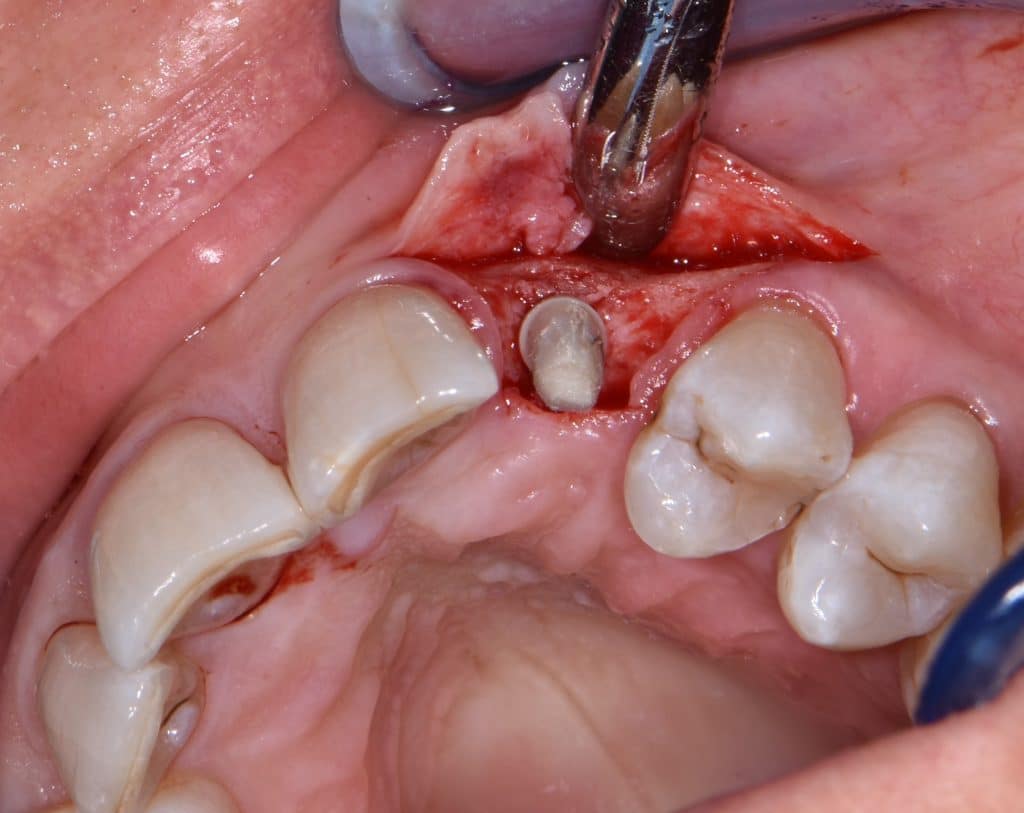

La pz N.G. di anni 52 (ASA 1) viene visitata nel mese di settembre 2017 per la mobilità ed inestetismo dell’elemento protesico 22, (foto iniziali sequenza 1) si evidenzia una frattura parziale della radice, si decide per l’estrazione ( foto sequenza 2) e sostituzione dell’elemento con un restauro implanto-protesico. Purtroppo la scarsa quota ossea apicale all’alveolo post-estrattivo (foto 2 rx) e l’alta valenza estetica dell’elemento ci rende cauti e si programma una socket preservation post estrattiva con l’ausilio delle membrane di prf (foto prf e socket sequenza 3 e 4). Durente i 5 mesi di guarigione la pz porta una protesi parziale mobile (foto 5,2) , a guarigione del sito post estrattivo si evidenzia una buona conservazione dei volumi osseo-gengivali,(foto guarigione sequenza 6) se pur presente una recessione distale all’elemnto 21.Nel mese di febbraio 2018 si procede all’inserimento di un impianto max-stability 3,75x12mm disegnando un lembo anticipato palatino per consentire un aumento dei tessuti vestibolari suturando con tecnica rool flap e trasformando l’elemento parziale mobile in una corona singola a carico immediato sul moncone temporameo applicando i concetti protesici bopt , (foto impianto moncone protesi provvisoria sequenza foto 7-8-9). Durante il periodo di maturazione dei tessuti molli vengono apportate opportune modifiche ai profili del provvisorio al fine di dare maggior spazio al tessuto gengivale, ( fotosequenza 10).Dopo circa 2 mesi dal protesizzazione provvisoria si è proceduto alla realizzazione del manufatto protesico con tecnica chair side sirona con l’ausilio del t-base (foto sequenza 11-12-13), realizzando in una sola seduta una corona in disilicato, ottenendo un risultato più che soddisfacente (Foto 14). Nel controllo a 3 mesi dal carico definitivo si apprezza la perfetta conservazione dei livelli ossei e gengivali. (foto sequenza 15).concludo con un follow up a 18 . Tengo a sottolineare che un caso come questo è stato conducibile con buoni risultati solo grazie alla piena fiducia della pz e alla sua massima motivazione e collaborazione. Ad oggi la pz sorride soddisfatta del risultato. E questo rappresenta la massima ricompensa di chi dedica tutto se stesso alla professione.